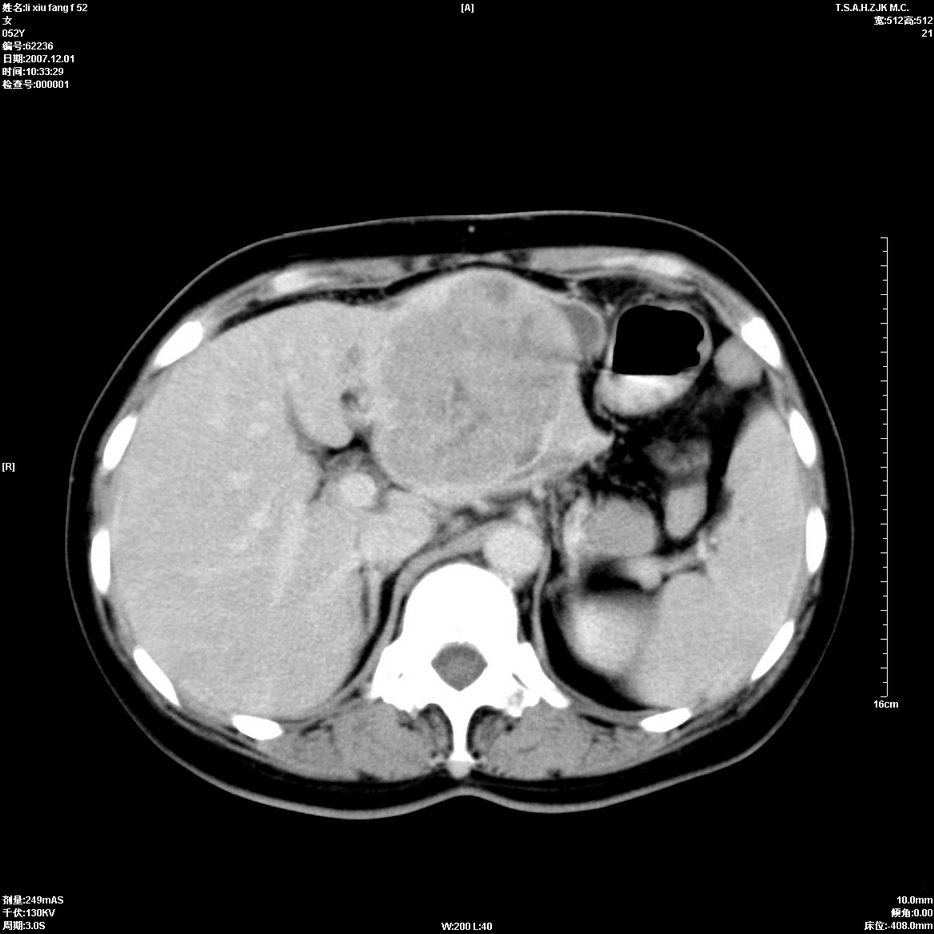

标题: CT12858:女,52岁,胎甲球蛋白861肝左叶占位,肝癌。下腔静 [打印本页]

标题: CT12858:女,52岁,胎甲球蛋白861肝左叶占位,肝癌。下腔静

肝左叶巨大低密度灶肿块,增强符合快进快出表现,有动静脉交通支;静脉期,下腔静脉内有充盈缺损,afp明显升高,支持肝癌并下腔静脉癌栓形成。

支持楼主   门静脉主干及左支癌栓形成

以下是引用拾荒者在2008-4-15 22:57:00的发言:[br]肝左叶巨大低密度灶肿块,增强符合快进快出表现,有动静脉交通支;静脉期,下腔静脉内有充盈缺损,afp明显升高,支持肝癌并下腔静脉癌栓形成。